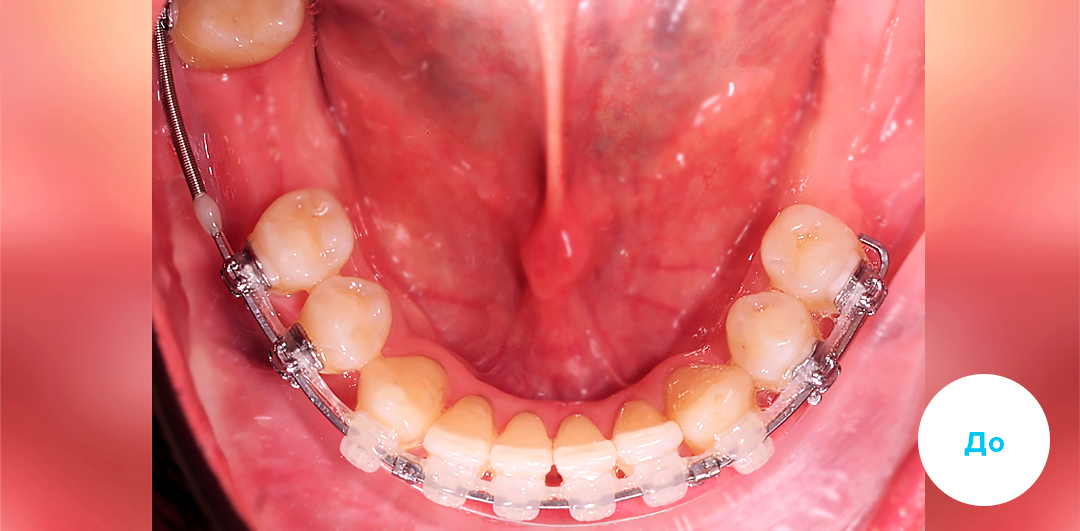

Результаты лечения